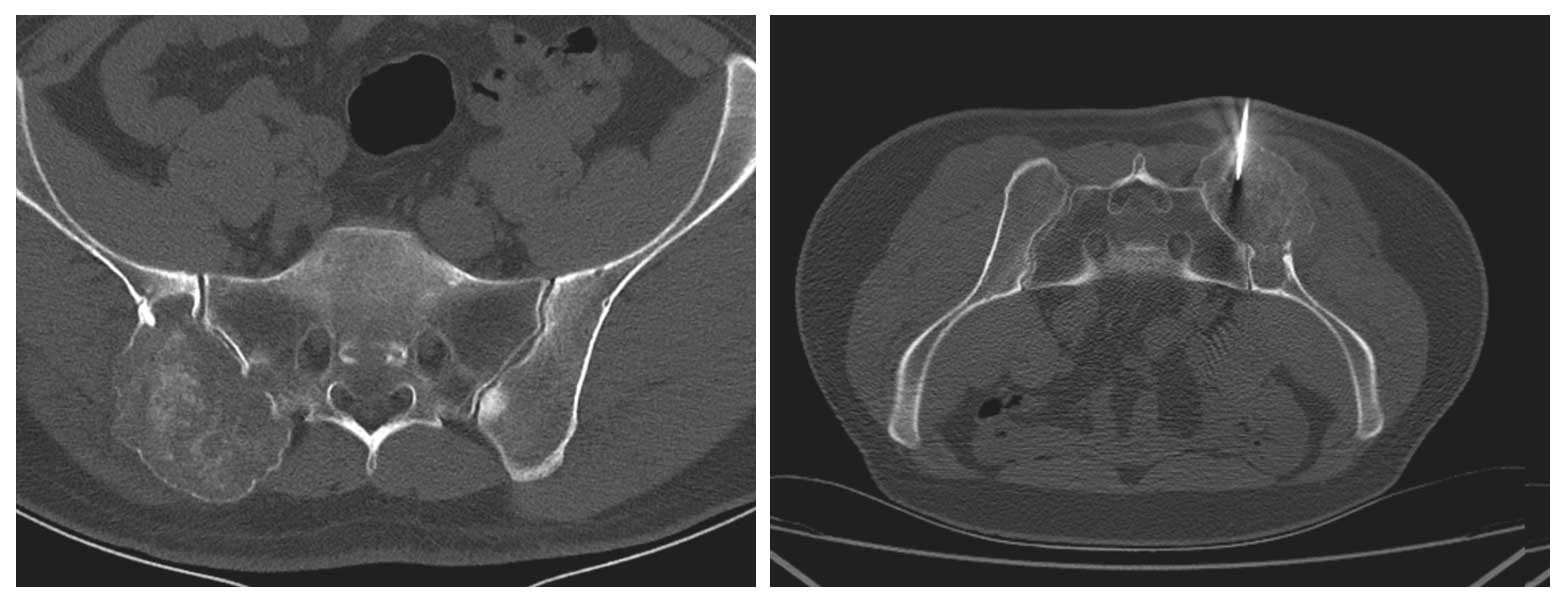

Ameliyat Öncesi: Tomografide sağ iliak kanat ve sakrum yerleşimli kemikte harabiyete neden olan tümör dokusu ve biyopsi iğnesi görülmekte.